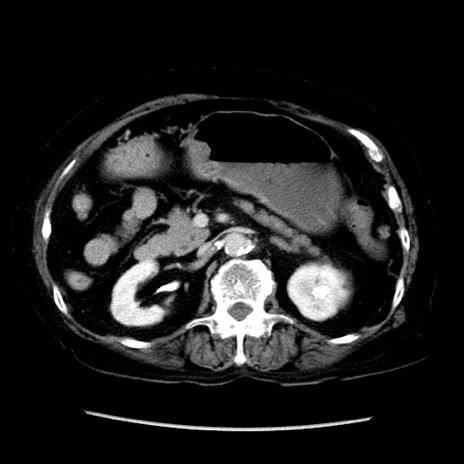

症例14(横断像)

【症例】 90歳代女性

【主訴】 腹痛・嘔吐

【現病歴】今朝から左側腹部痛を認めた。 経過観察していたが、嘔吐を認めたため来院。

【既往歴】 子宮癌術後

【身体所見】 意識清明、BP 127/54mmHg、P 98bpm Sp02 95%(RA)、BT 35.8°C、腹部平坦・軟腸ぜん動音聴取良好、右下腹部圧痛(+) 反跳痛なし

【データ】WBC 9800、CRP 0.46